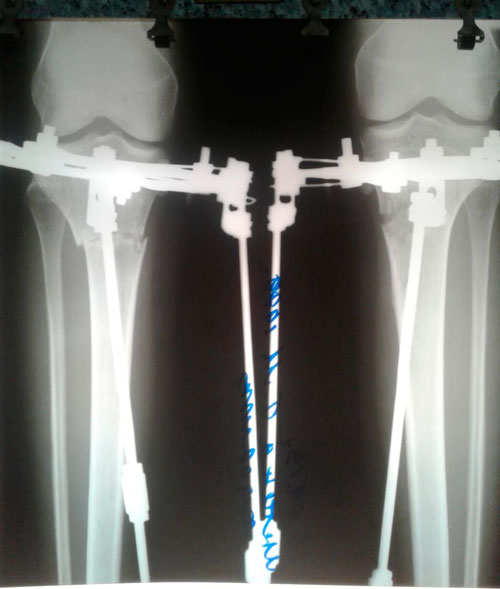

Пациентка - 30 лет.

Дата операции - 04.04.2019г.

Дата снятия аппаратов - 02.07.2019г.

Срок сращения - 89 дней.